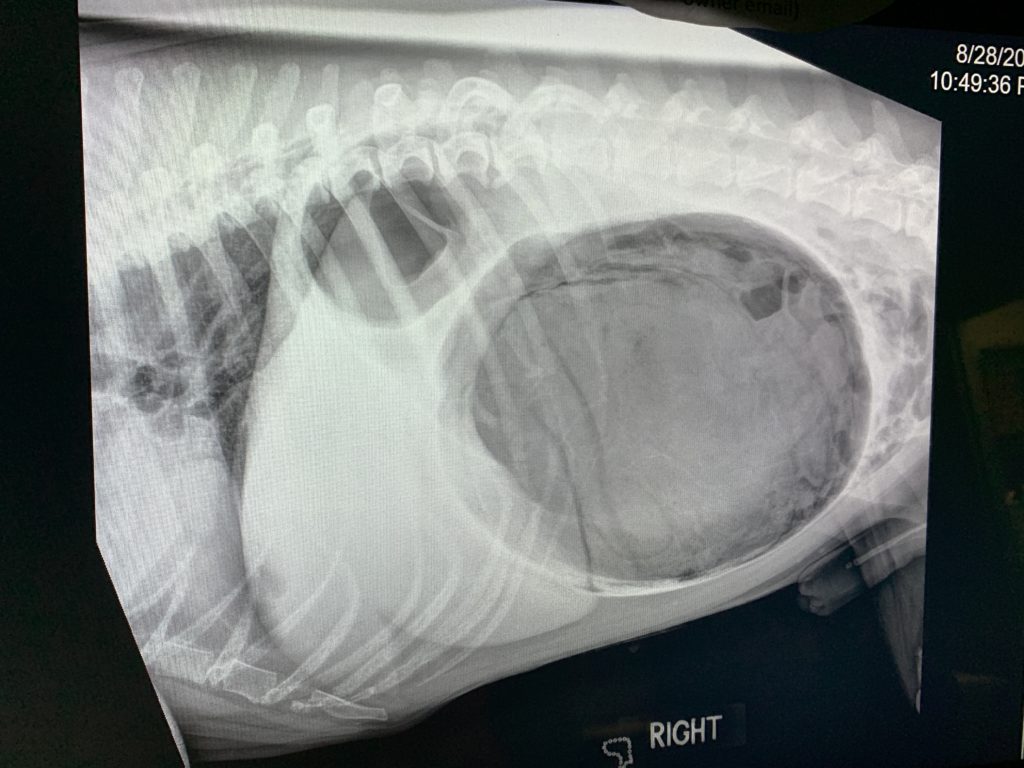

Dog Bloat X Ray . As the stomach fills with air, pressure builds, stopping blood from the. Animals critical with gdv are high anaesthetic risks, so your vet may use. What is bloat in dogs? It is also known as gastric torsion, gastric dilatation volvulus, or canine gdv and it is one of the most serious pet emergencies. Wendt, and recommend the right treatment. Your vet can determine the difference between fluid buildup and bloat with a physical exam according to dr. Fluid buildup in the abdomen (ascites): Understanding the dog bloat timeline and taking swift action can significantly impact the outcome for your dog. This condition can give your dog’s stomach a similarly distended appearance.

DOG STOMACH BLOAT and TORSION XRAY Stock Photo Image of animal Dog Bloat X Ray Understanding the dog bloat timeline and taking swift action can significantly impact the outcome for your dog. Wendt, and recommend the right treatment. Animals critical with gdv are high anaesthetic risks, so your vet may use. Fluid buildup in the abdomen (ascites): Your vet can determine the difference between fluid buildup and bloat with a physical exam according to dr.. Dog Bloat X Ray.